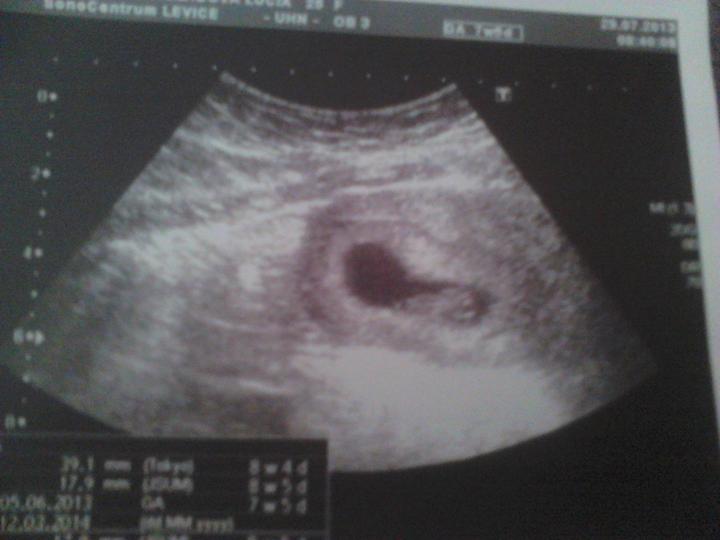

nasa miska bude na svete 3,3 2014

nasa malickaMiška ma 1800g a budem rodit znova cisarskym

budeme mat dievcatko na 100percent